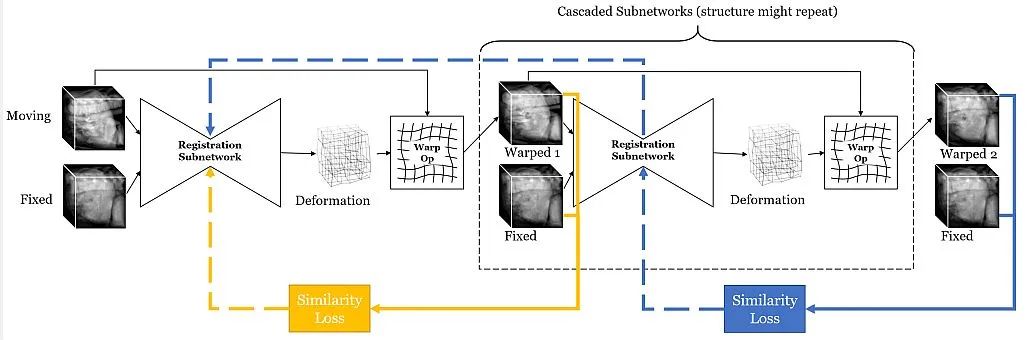

基于深度学习的配准: 它应用卷积神经网络(CNNs)直接从图像对学习变换。它可以处理复杂的变换和大数据集,但需要额外的训练数据。此外,在训练期间计算成本较高。

医学图像配准旨在找到最佳的空间变换,以最佳地对齐现有的解剖结构。它被广泛应用于许多临床应用中,例如图像重建、图像引导、运动跟踪、分割、剂量积累等。医学图像配准是一个宽泛的主题,可以从不同的角度来考虑。

从输入图像的角度来看,配准方法可以分为单模态、多模态、跨患者和同患者配准。从变形模型的角度来看,配准方法可以分为刚性、仿射和可变形方法。从感兴趣区域(ROI)的角度来看,配准方法可以根据解剖部位分组,例如大脑、肺部配准等。